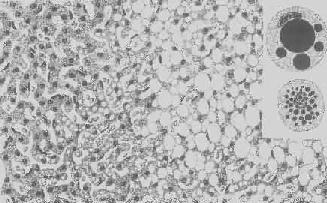

肝淀粉样变

图1-22 肝淀粉样变

淀粉样物质呈均质状,沉着于窦内皮下,肝细胞索受压萎缩